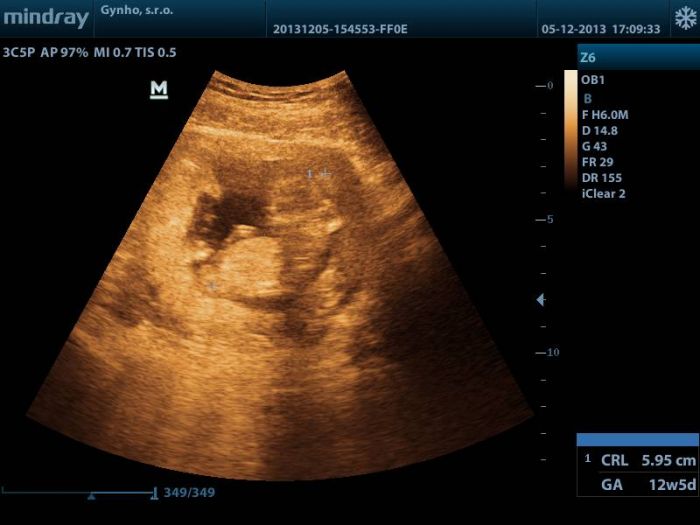

Ahojte holky, tak dneska jsem byla na kontrole u sveho Dr, delal mi utz pres bricho, takze obrazek nic moc, ale i tam prikladam